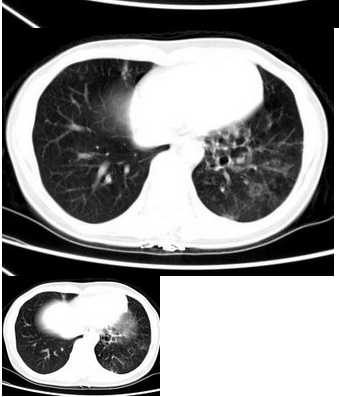

说到应用层面,医学影像技术CT理论在临床里可是个“万能钥匙”。比如在急诊科,CT快速扫描能帮医生判断脑出血或骨折,救命于分秒之间。俺们医院的老王医生常念叨:“不懂CT理论,就像开车不看路标,瞎转悠容易出岔子。”所以,深入学习医学影像技术CT理论,能让咱们在操作设备时更得心应手,解决了实际工作中理论脱节的痛点——您想想,要是只会按按钮,不懂背后门道,那跟蒙眼走路有啥区别?俺当初学的时候,可没少为这个掉头发,但现在回头一看,真是值当!通过理论整理,您会发现CT在肿瘤检测、血管成像中都能大显身手,甚至能指导手术规划,让治疗更精准。这可不是吹牛,俺亲身经历过一个案例:一位患者肺部有微小结节,靠CT理论优化扫描参数,图像清晰得连细节都一清二楚,最终早期确诊,避免了病情恶化。这种成就感,真是让人热血沸腾啊!